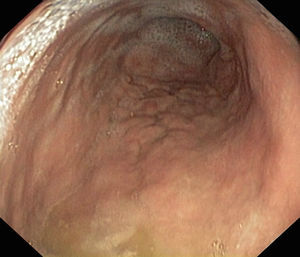

Se presenta un varón de 11 años que consulta por plenitud posprandial y sensación nauseosa de 3 años de evolución, sin vómitos, pirosis, ni dolor abdominal. Hábito intestinal y desarrollo normales. Refiere orquiepididimitis de repetición (biopsia testicular y de epidídimo normal) y pólipo de retención a los 3 años. Antecedentes familiares de enfermedad autoinmune (madre: EII inespecífica, gastritis crónica y artritis; padre: artritis psoriásica; rama materna: gastritis crónica, anemia perniciosa, síndrome de Sjögren y enfermedad celíaca). Exploraciones complementarias: hemoglobina 13,3g/dl; ferritina 15μg/l; vitamina B12 150pcg/ml. Niveles bajos de pepsinógeno I: 3,5ng/ml; pepsinógeno II: 6,3ng/ml y gastrina: 19,6pg/ml. Hemograma, bioquímica, coagulación, hormonas tiroideas e inmunoglobulinas normales. Anticuerpos ANA, ANCA, ASCA, antitransglutaminasa IgA, anticélulas parietales, anti-LKM, antimúsculo liso, antimitocondrial y antifactor intrínseco negativos. Calprotectina fecal normal. La endoscopia alta demostró mucosa pangástrica con pliegues engrosados y aspecto nodular (fig. 1). Biopsia gástrica: infiltrado de células inflamatorias y gruesa banda colágena subepitelial y marcada atrofia glandular oxíntica. No se observó Helicobacter pylori, metaplasia enteroide ni displasia epitelial (fig. 2). La colonoscopia descartó afectación colónica. El paciente estaba asintomático, por lo que se mantuvo tratamiento con vitamina B12 y hierro. Se realizaron endoscopias de seguimiento a los 6 y 18 meses en las que se demostró la persistencia de gastritis colágena, manteniéndose asintomático.

El diagnóstico exige realizar una endoscopia digestiva superior y se recomienda colonoscopia para descartar afectación colónica asociada. Los hallazgos histológicos incluyen un infiltrado inflamatorio crónico subepitelial junto con una banda de colágeno mayor de 10 micras. El aspecto nodular de antro y cuerpo gástricos es típico y más frecuente en niños5. También se puede observar una mucosa eritematosa, acompañada de seudopólipos, erosiones, úlceras o sangrado. El curso de la enfermedad es crónico, aunque benigno. No se han descrito malignizaciones evolutivas, aunque la historia natural de la enfermedad es desconocida6.